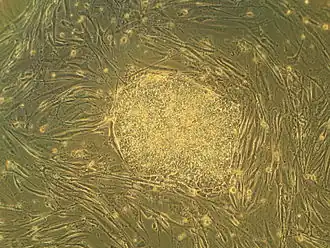

Biological breakthroughs

The discovery of insulin at the University of Toronto by Banting and Best in 1921 is considered among the most significant events in the history of medicine.[14][160] The stem cell was discovered at the university in 1963, forming the basis for bone marrow transplantation and all subsequent research on adult and embryonic stem cells.[161] This was the first of many findings at Toronto relating to stem cells, including the identification of pancreatic and retinal stem cells.[162][163] The cancer stem cell was first identified in 1997 by Toronto researchers,[164] who have since found stem cell associations in leukemia, brain tumours and colorectal cancer.[165][166] Medical inventions developed at Toronto include the glycaemic index,[167] the infant cereal Pablum,[168] the use of protective hypothermia in open heart surgery[16] and the first artificial cardiac pacemaker.[16] The first successful single-lung transplant was performed at Toronto in 1981, followed by the first nerve transplant in 1988,[169] and the first double-lung transplant in 1989. Researchers identified the maturation promoting factor that regulates cell division, and discovered the T-cell receptor, which triggers responses of the immune system.[170] The university is credited with isolating the genes that cause Fanconi anemia, cystic fibrosis and early-onset Alzheimer's disease, among numerous other diseases.[171] Between 1914 and 1972, the university operated the Connaught Medical Research Laboratories, now part of the pharmaceutical corporation Sanofi-Aventis. Among the research conducted at the laboratory was the development of gel electrophoresis.[172]